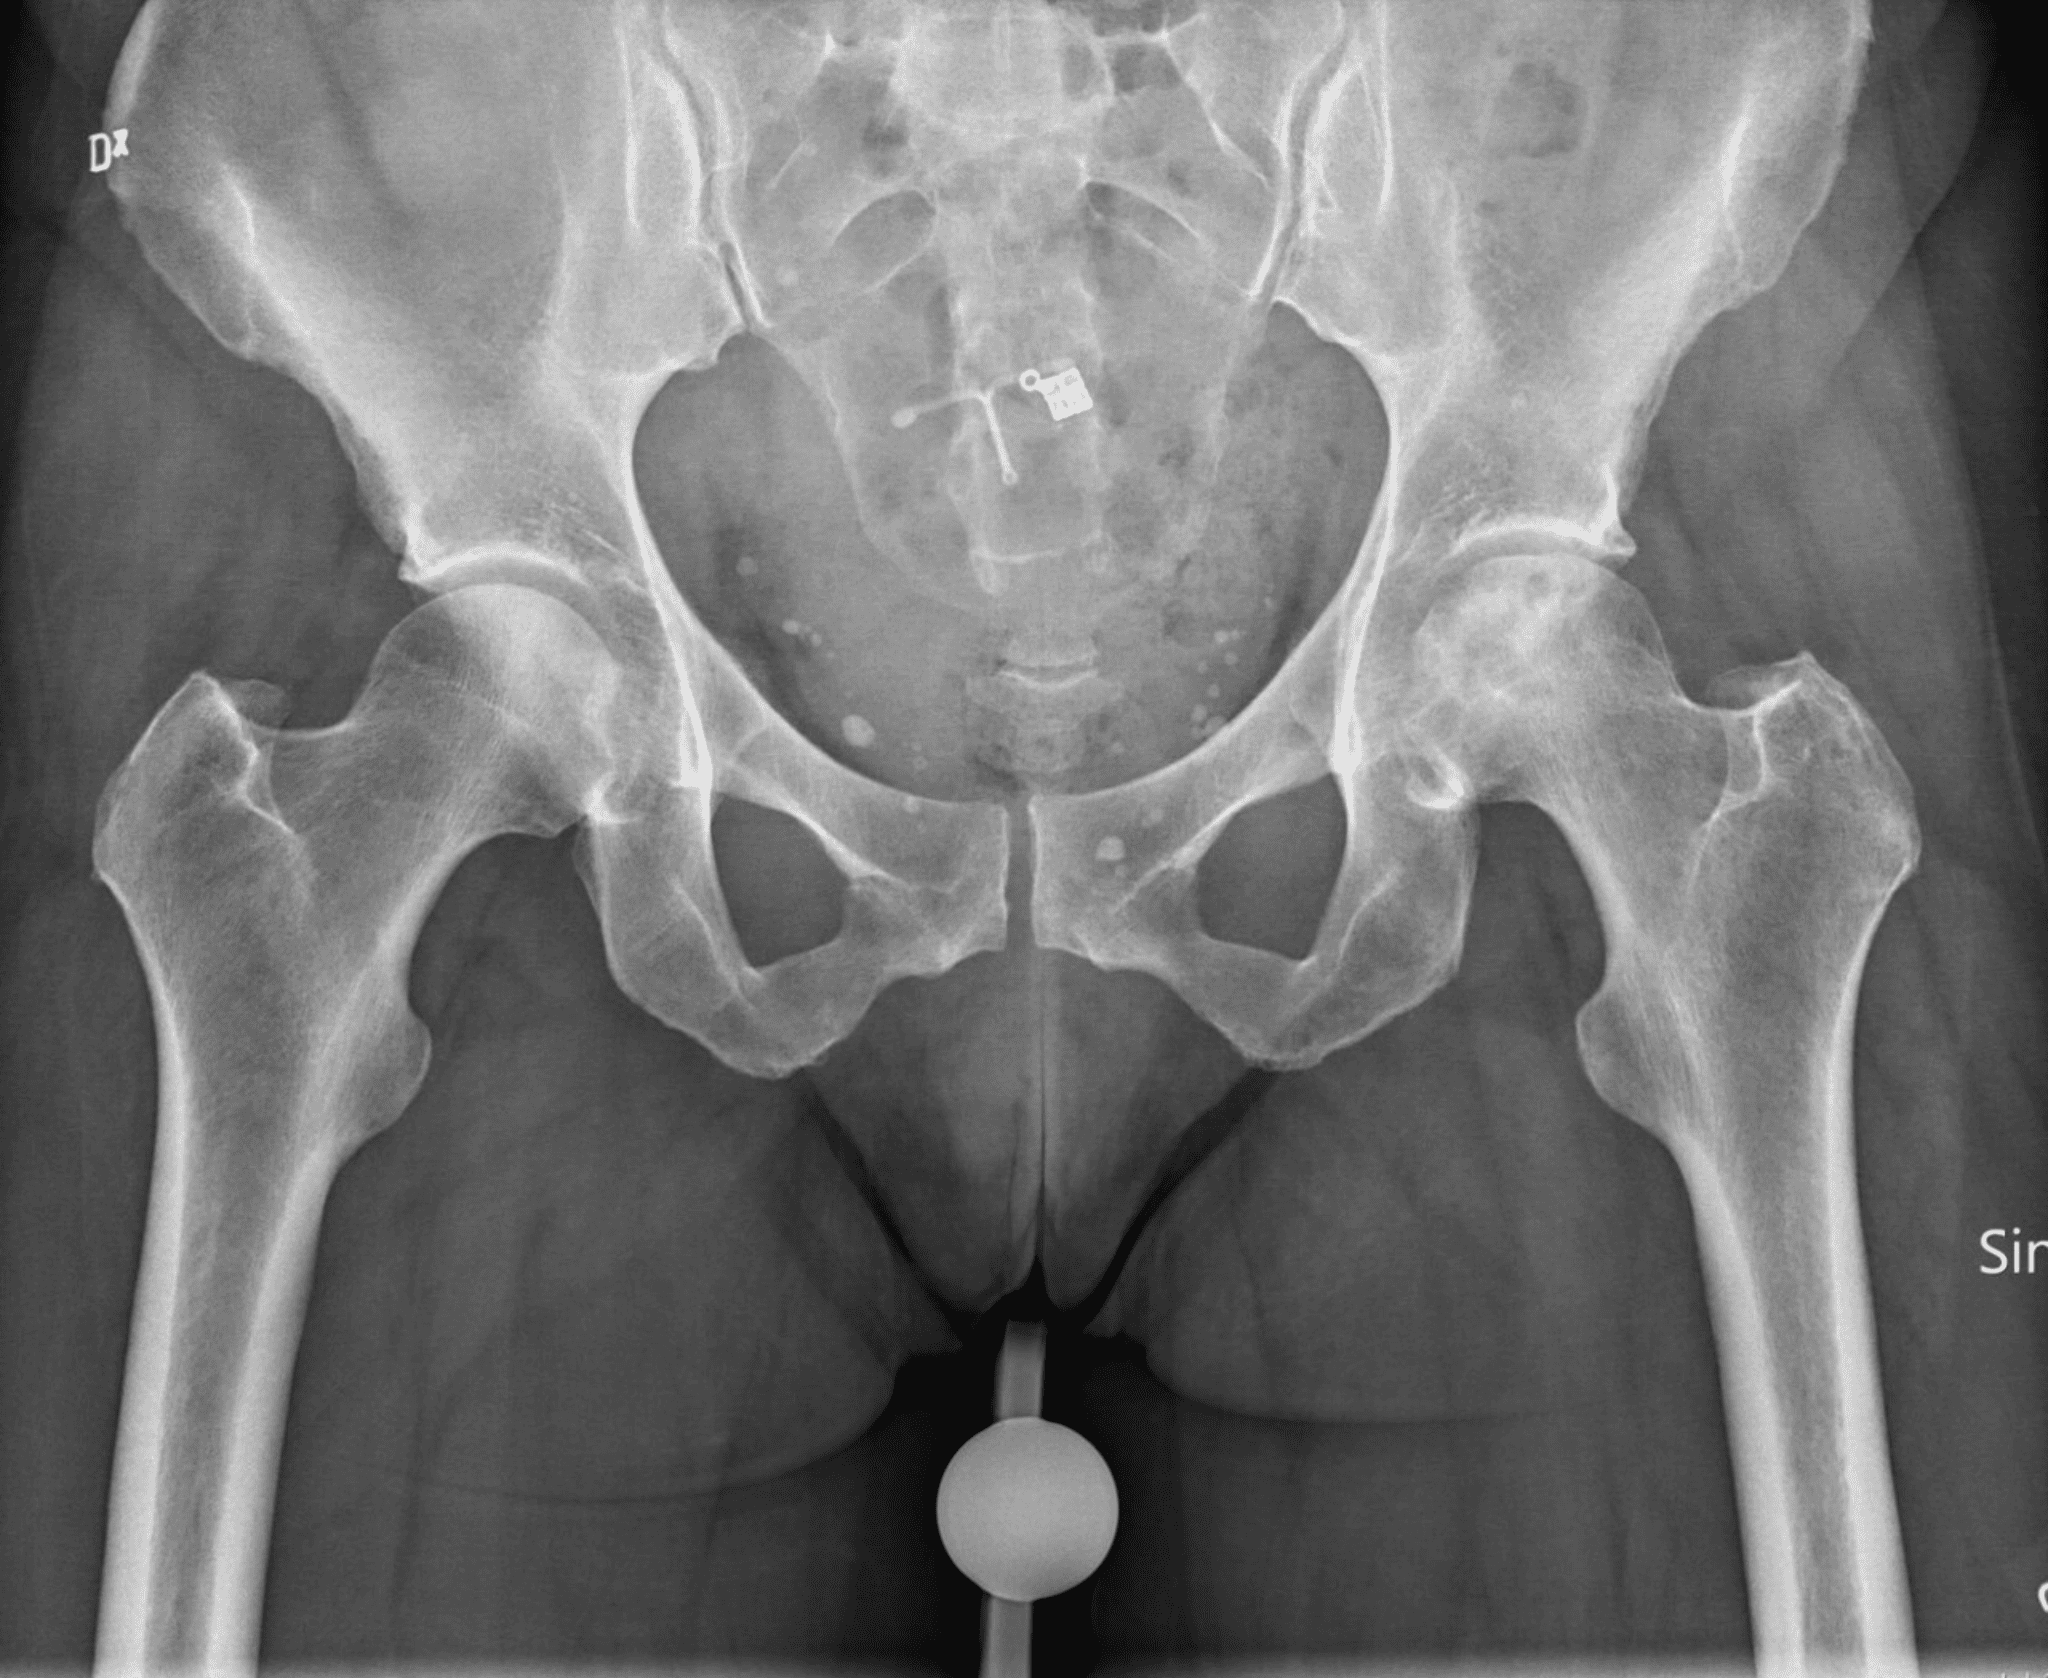

Röntgenfoto: soms te laat zichtbaar

Een gewone röntgenfoto is vaak de eerste stap. In een vroeg stadium kan die nog normaal lijken. Dat is het verraderlijke. Pas wanneer het bot begint in te zakken of wanneer de vorm van de heupkop verandert, worden afwijkingen zichtbaar.

Je ziet dan bijvoorbeeld:

- Afvlakking van de heupkop

- Een sikkelvormige lijn onder het kraakbeen, het zogenaamde crescent sign

- Tekenen van beginnende artrose

Maar in de eerste fase kan de schade zich al afspelen terwijl de foto niets laat zien.